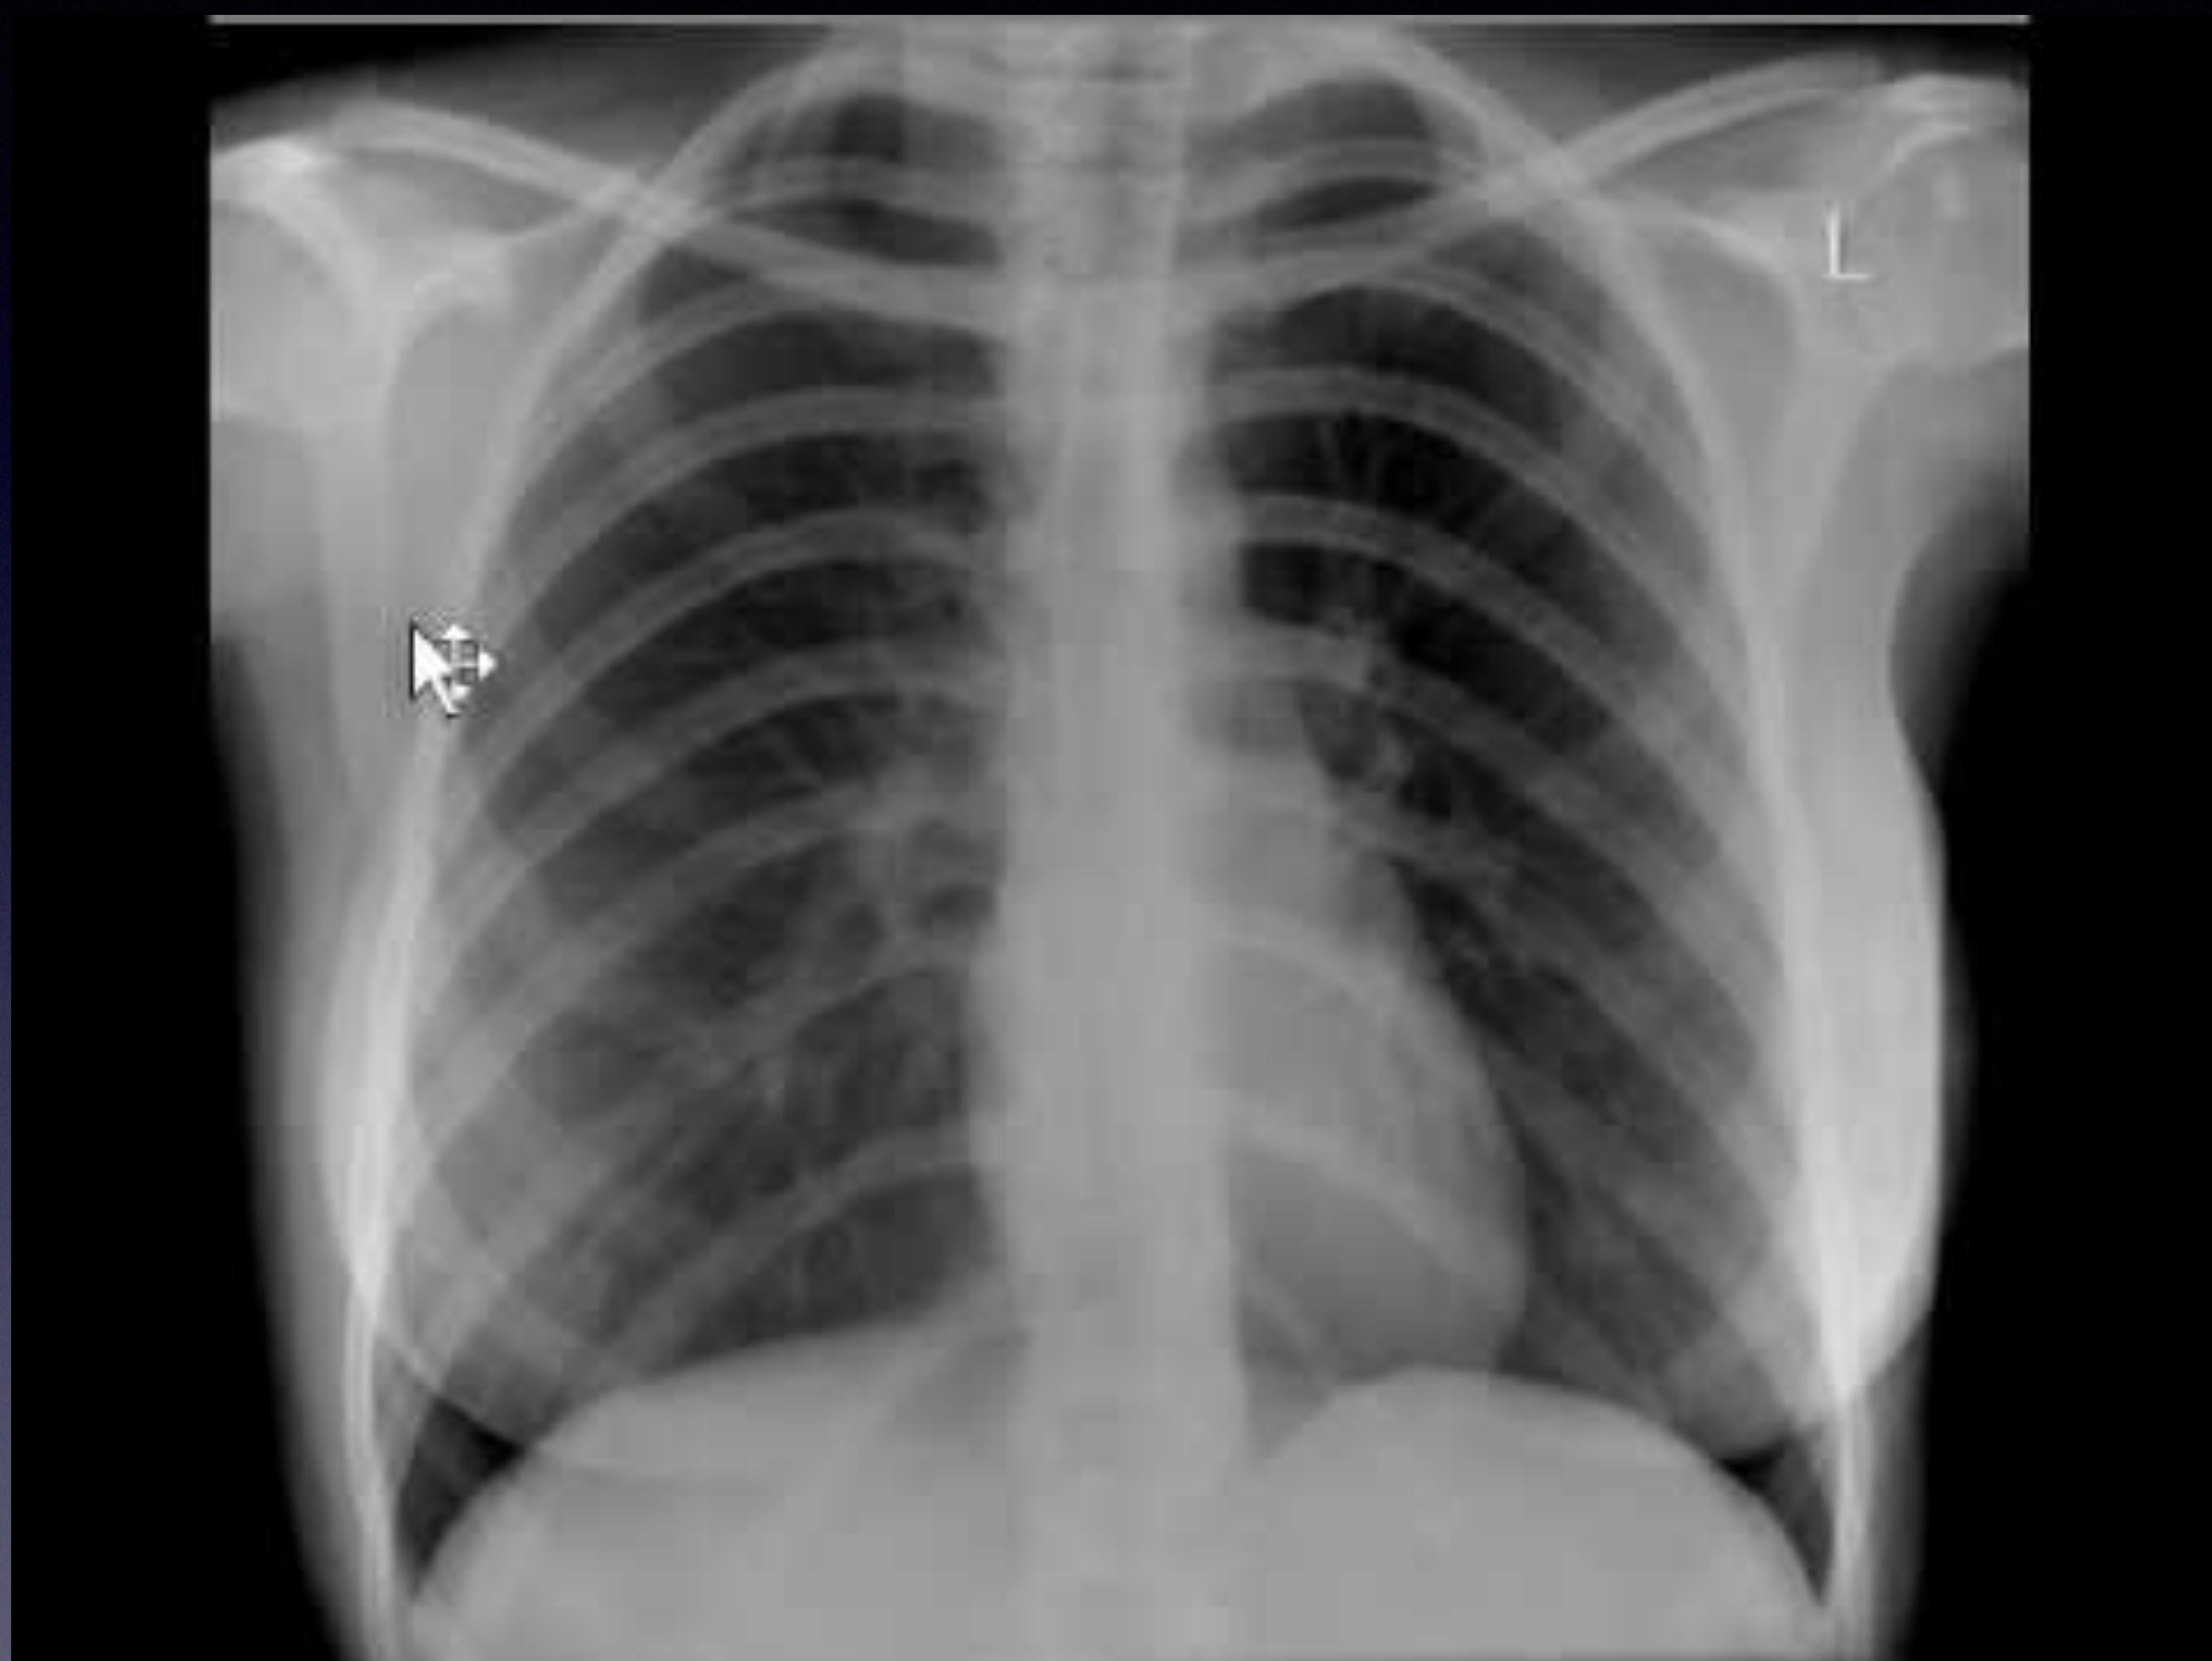

2. X-ray

- Chest X-ray

- Pelvic X-ray

Anteroposterior chest X-ray showing a suggestive pulmonary nodule/mass.